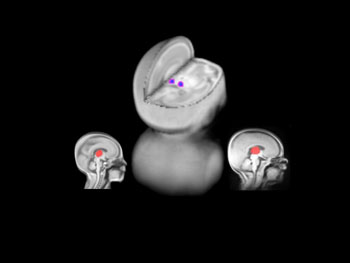

Using magnetic resonance imaging to study brain growth in very preterm babies we found that a specialized region of the brain (red), the thalamus (involved in relaying pain and touch information to the brain) showed a decrease in size (blue-purple) in those babies exposed to more painful procedures. Further, babies born at less than 28 weeks of gestation had the most pronounced changes in the thalamus.